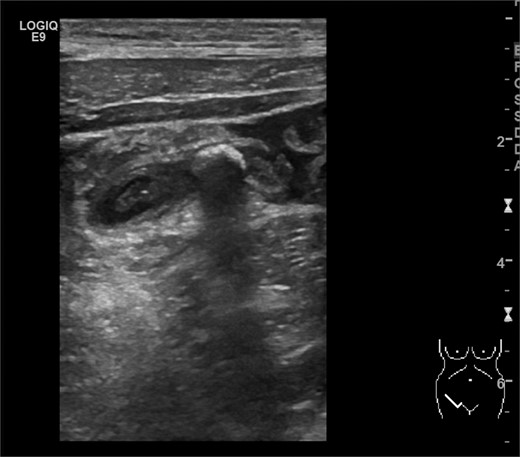

Physical examination revealed normal vital signs, severe diffuse right abdominal tenderness, generalized rebound tenderness, guarding accentuated in the right lower abdomen and rare bowel movements. Laboratory evaluation showed a slightly elevated C-reactive protein (CRP) (17 mg/l, reference <5 mg/l) and an elevated leukocyte count (18 000 cell/mm3, reference <10 200 cell/mm3). Transvaginal and transabdominal ultrasound scanning revealed a normal uterus, a small fluid collection in the Douglas space, an already normal-appearing right ovary, no free fluid in the Morison’s pouch, no pathology of the gallbladder and no lesions suspected to be an abscess. But it showed an increased diameter of the appendix of 8.2 mm, “target sign” on axial scan of the appendix, an appendicolith and periappendiceal fluid of ~2 ml (Fig. 2). Therefore, an immediate re-laparoscopy was indicated, which showed an acute appendicitis and peritonitis (Fig. 3). A laparoscopic appendectomy was performed. The postoperative period was uneventful and the patient was discharged without complication. Pathologic evaluation of the appendix showed an ulcero-phlegmonous, partly abscessing appendicitis, a distal appendicolith of 0.5 cm in diameter and acute peritonitis.

Ultrasonography showing the appendicolith and periappendiceal fluids. (Picture by Markus Buerge, MD)